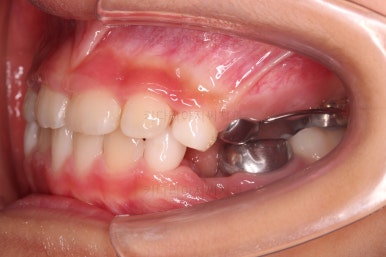

부산어린이반대교합 이번에 사용한 장치는 메탈 브라켓이며 테크닉적으로는 투 바이 포 교정이라고 합니다.(2x4)

삐뚤어진 앞니를 가지런히 하면서 아랫니 보다 뒤에 있는 윗니의 위치를 바로 잡아 주는거죠.

벌써 치료가 종료되었네요ㅎㅎ

총 4개월 걸렸습니다.

반대교합만 고쳐준 것이 아니라 기왕 하는김에 치열을 가지런히 해줬고요.

(아래 치열은 장치를 부착해주지도 않았는데 자연스럽게 처음보다 가지런해졌죠? ^^)